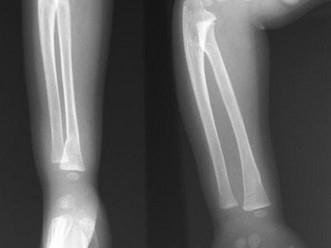

出生6个月的男婴,摔地后右手红肿,请结合CR片,选出骨折类型 ( )A、粉碎性骨折B、压缩骨折C、横行骨折D、斜行骨折E、青枝骨折

问题 出生6个月的男婴,摔地后右手红肿,请结合CR片,选出骨折类型 ( )

选项 A、粉碎性骨折 B、压缩骨折 C、横行骨折 D、斜行骨折 E、青枝骨折

答案 E